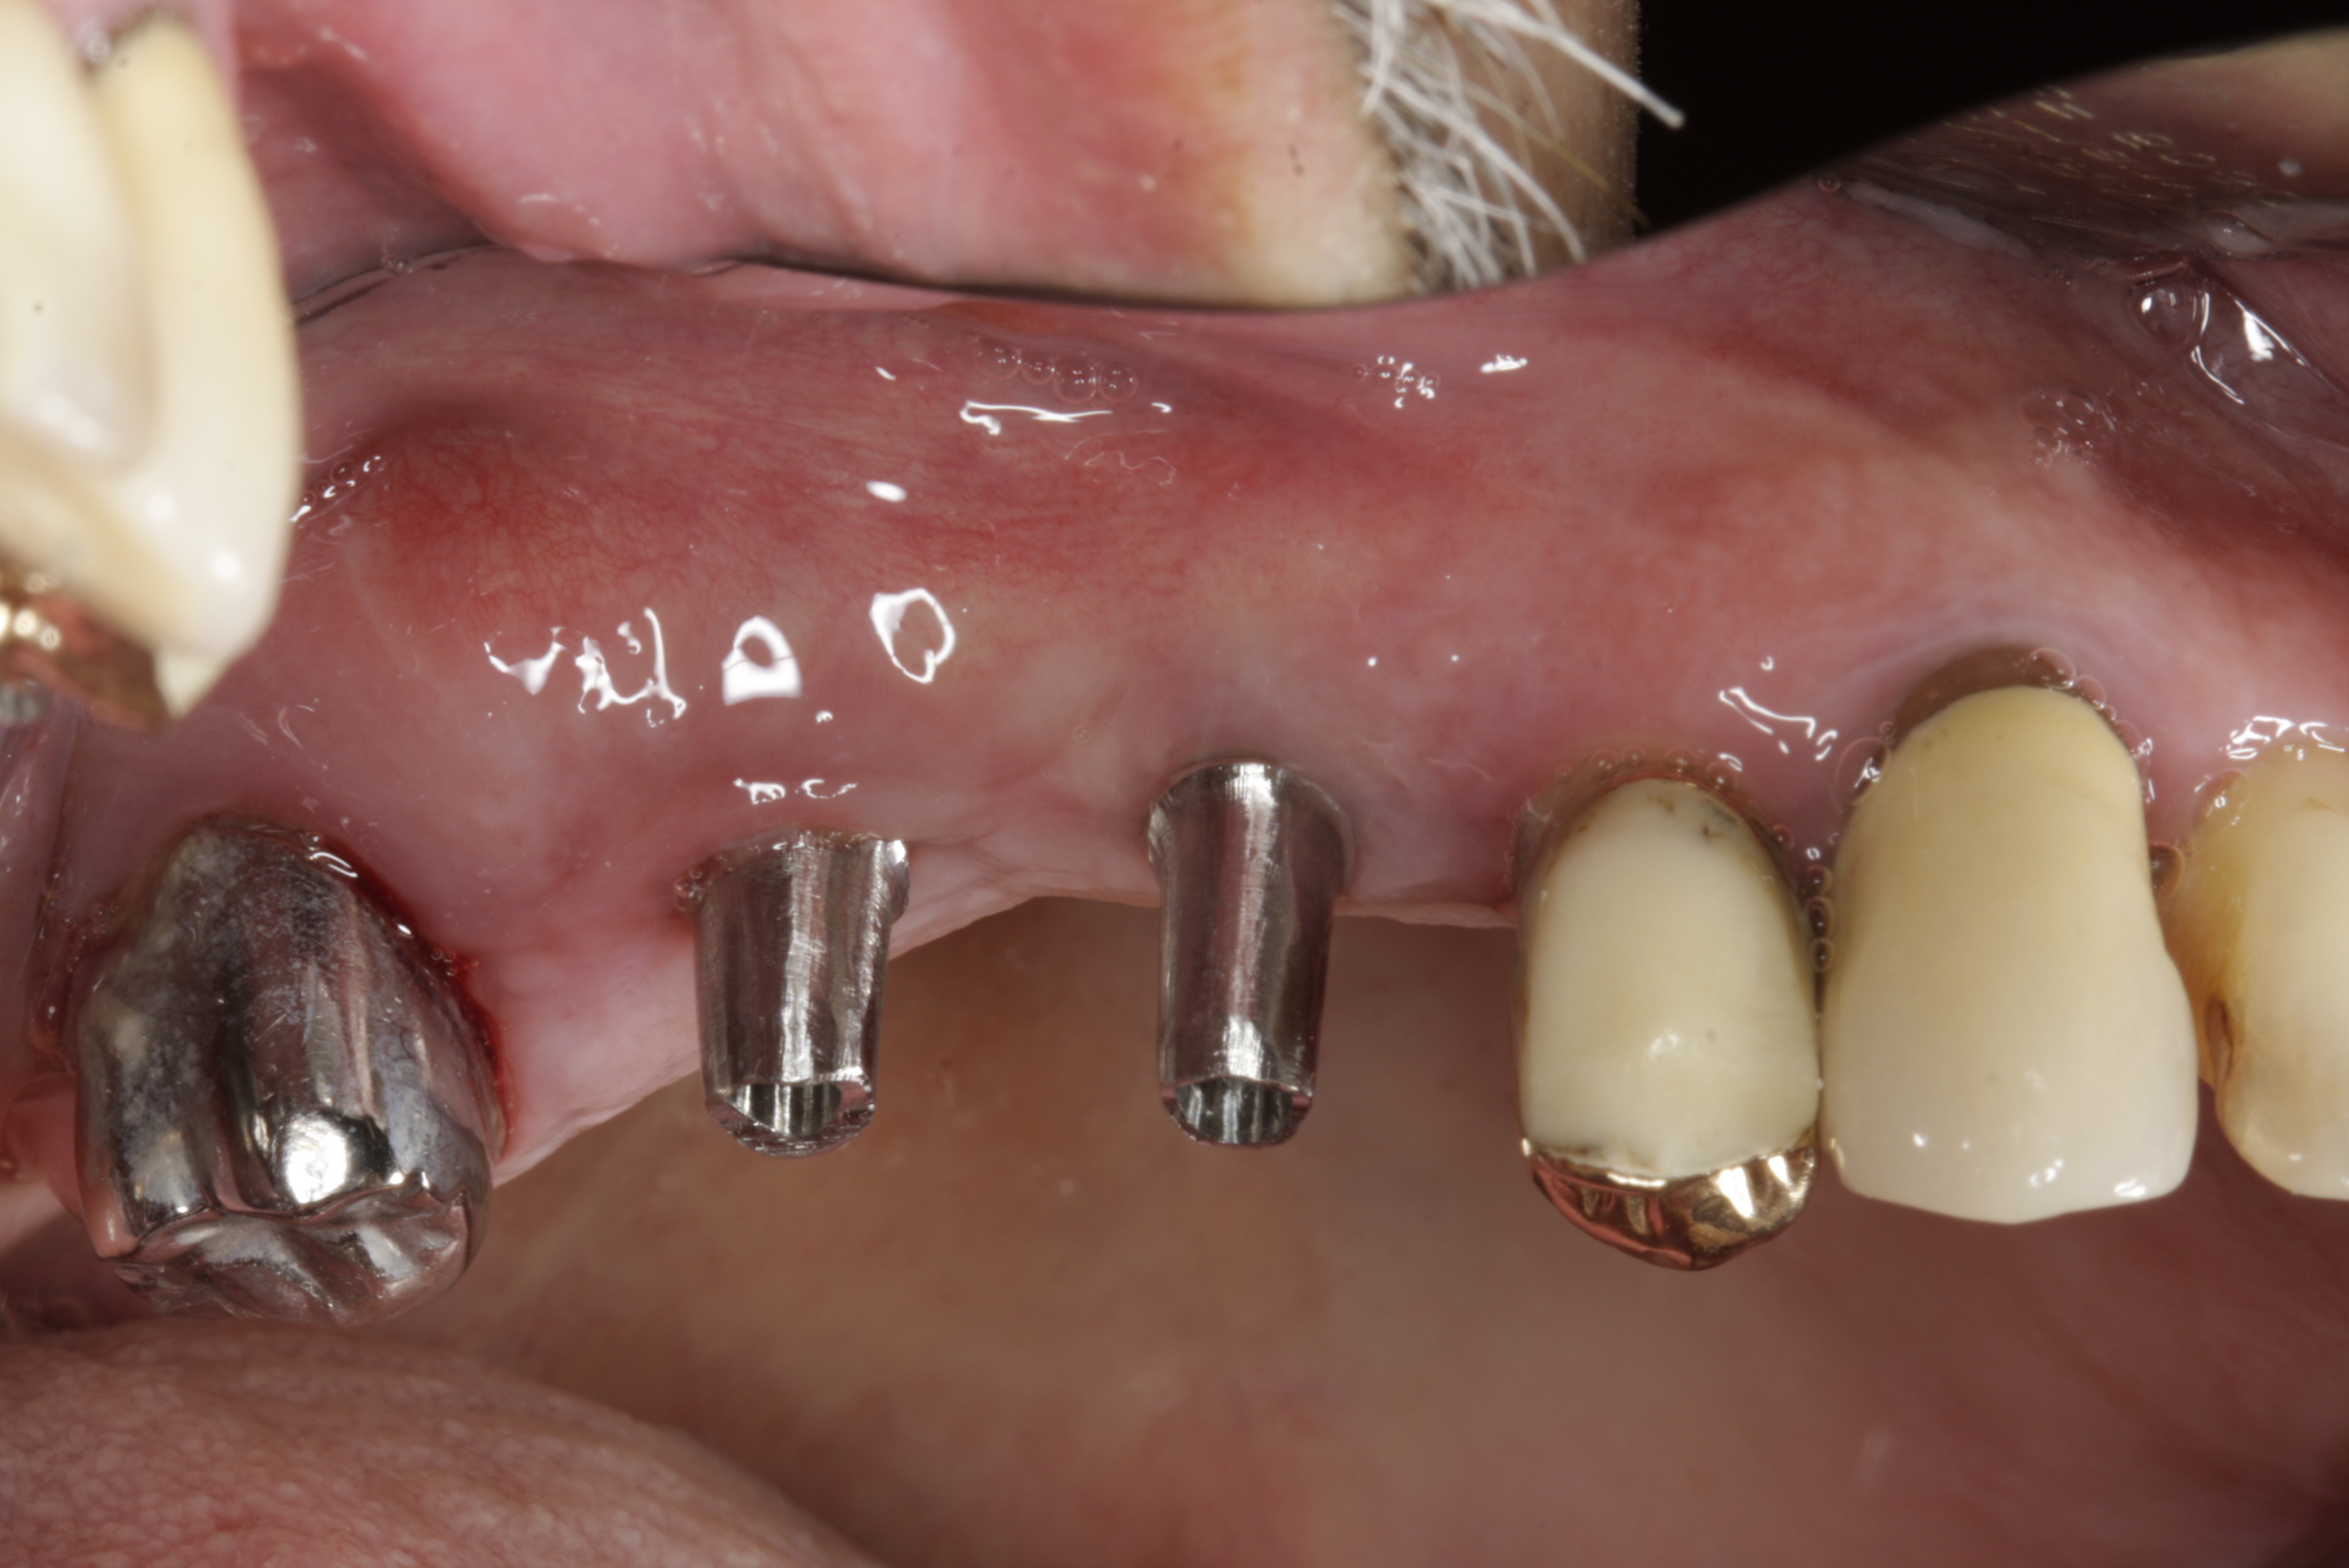

Bezzubá čelist je hlavní indikací pro ošetření pomocí implantátů. Zejména celkové zubní náhrady v dolní čelisti mají velice nízkou stabilitu a držení díky velkému úbytku kosti.

S pomocí zubních implantátů můžeme díky různým kotevním systémům (třmeny, kulové hlavy, Locatory) zajistit stabilitu a držení protézy nebo při použití většího počtu implantátů zhotovit pevné náhrady – můstky nalepené nebo našroubované na pevno na implantáty.